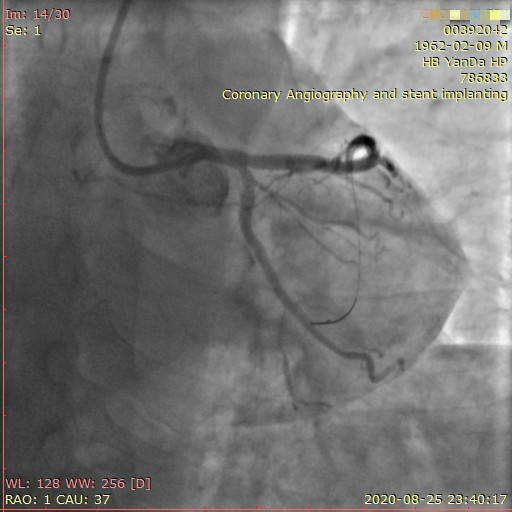

李先生右冠術前影像

術前,翟光耀主任還親自為李先生復查冠狀動脈造影,造影結果顯示:患者的前降支、回旋支、右冠等冠脈三支嚴重病變、嚴重鈣化,且均為彌漫性長病變,最重處99%以上管腔極嚴重狹窄。翟主任仔細閱讀造影結果后指出:結合李先生的實際情況,雖然微創介入手術難度比較大,但仍可行;李先生心臟三支主干動脈均存在極其嚴重的狹窄,每一支動脈均至少植入2-3枚支架,根據患者的耐受情況,李先生可能需要分3次分別對三支動脈進行介入手術;考慮到李先生路途遙遠,病情嚴重,不宜反復奔波,并且患者迫切要求能夠徹 底解決病痛,在病情允許的情況下,如果手術順利,爭取為患者進行“一站式”手術,一 次 性解決全部三支動脈病變!

李先生足位術前影像

李先生足位術后影像

手術方案確定之后,在心血管內三科趙景新主任、介入醫學科富孝晨主任的配合下,翟光耀主任親自擔任主刀,分別依次對李先生的三支動脈進行了完全血運重建。由于手術進展順利,李先生術中沒有任何癥狀,耐受良好,于是成功的將三支動脈“一站式”治療!術中,由于李先生左主干遠端分叉處存在嚴重病變,翟光耀主任選擇國際指南推薦的DK-mini-Crush技術,確保了分叉處兩支主干開口均萬無一失。據悉,DK-mini-Crush技術是目前冠脈分叉病變領域最為復雜及難以掌握的介入技術之一,對手術醫生經驗、體力均提出了極大的挑戰。極為擅長復雜介入技術的翟光耀主任卻用嫻熟的技術確保了李先生手術的成功。

冠狀動脈嚴重鈣化合并狹窄病變是冠脈介入的一大難題,血運重建難度大,成功率低,并發癥發生率高,該例患者的成功救治標志著我院冠脈介入水平又躍上了一個新的臺階。